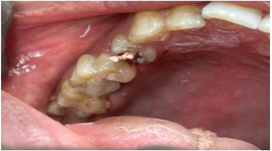

Root Canal Therapy - #16, #46, #14 (Figure 3)

Figure 3: Clinical photograph taken during procedure #14